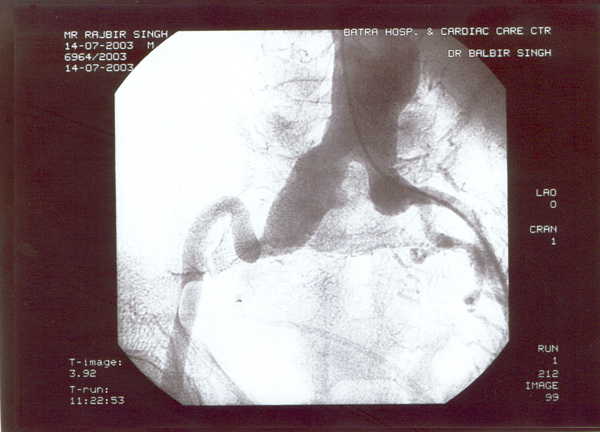

Case presentation

- Rajbir Singh, 60 yrs male.

- Abdominal pain for years now worsening.

- Severe COPD + PHT + CAD.

- USS abdomen for abdo pain – 7cm AAA.

- Pulsatile abdominal mass – non tender.

- All peripheral pulses palpable to ankles.

- No complications – blue toe syndrome.